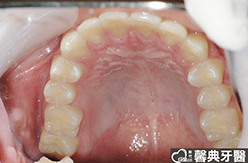

患者︰黃小弟弟,十三歲,學生。

主訴︰戽斗,想做矯正。

治療計劃︰上顎前牙排齊後彈出,下顎前牙排齊後後縮,重建正常咬合關係。